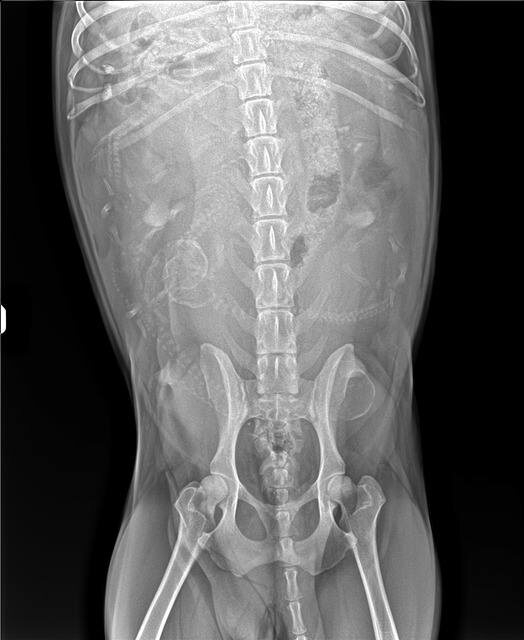

На всякий случай сделали рентген, исключить наличие инородных предметов.

И заодно посчитали щеночков❤️❤️❤️

Готовлю местечко для малышей и мамочки и разглядываю снимки😀 Я насчитала 5 щеночков, а вы?)))))